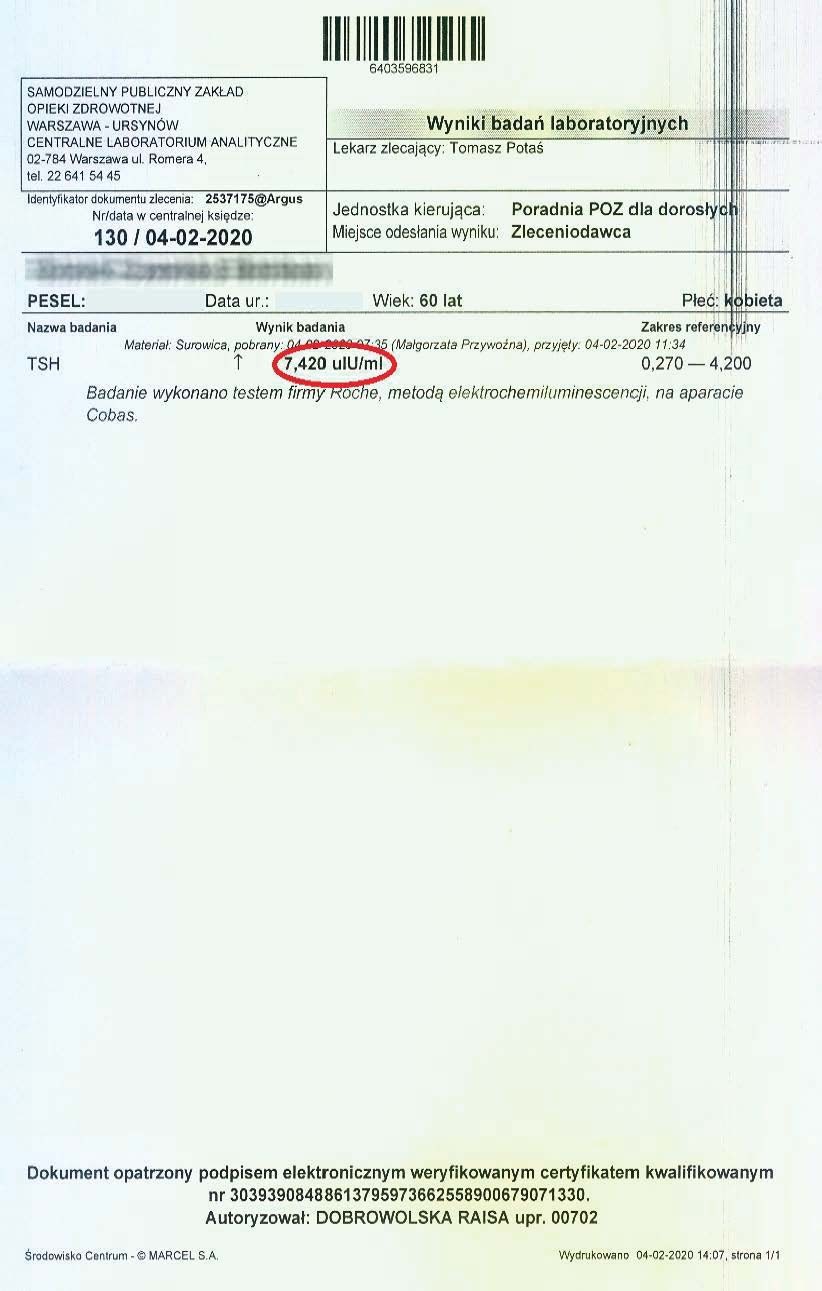

PRZYKŁAD EFEKTU PREPARATU NA NIEDOCZYNNOŚĆ TARCZYCY

Kobieta lat 59 z niedoczynnoscią tarczycy, bez przyjmowania lewotyroksyny. Kobieta przyjmowała preparat przez okres ponad 3 miesięcy. Przy zachowaniu naturalnego cyklu komórkowego i stałemu stymulowaniu mitochondriów osiągneła następujące wyniki kuracji:

Po zaobserwowaniu znacznej poprawy w ogólnym samopoczuciu, kobieta postanowiła wykonywać badania ze zwiększoną częstotliwością oraz kontrolę prób wątrobowych.

Po kolejnych dwóch miesiącach kobieta ponownie wykonała badania. Widoczne są: spadek TSH, obniżenie stanu zapalnego jak i spadek markeru wątrobowego GGTP.

Sukcesywnie co 2 miesiące można zaobserwować stały spadek parametrów zarówno wątroby jak i tarczycy. Kolejne badania potwierdzały dalszy spadek parametrów.

Po ponad roku kuracji badania wykazały dalszy postęp wycofania autoimmunologi tarczycy, potwierdzone również badaniem USG narządu.

Preparat wpływając na odbudowę mitochondriów zapewnił podłoże energetyczne do produkcji hormonów i odbudowy narządu. Brak ingerencji farmakologicznej wykazuje skuteczność nawet w podeszłym wieku, gdzie regeneracja jest wolniejsza a reakcje anaboliczne w znacznym stopniu spowolnione. Można zaobserwować także działanie ogólnoustrojowe obserwując spadek markeru wątroby, co jasno wykazuje poprawę funkcjonowania całego organizmu.